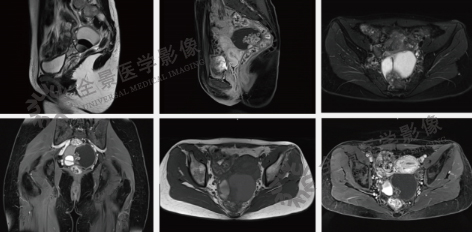

MRI能显示盆腔的解剖结构,为男、女性盆腔肿瘤、炎症、转移等病变,提供重要的诊断依据。

案例:中年女性,体检超声发现右侧卵巢囊肿3年余,无自觉不适,月经周期及量均无异常;4个月前复查超声示子宫右后方囊实性肿块,考虑恶性肿瘤可能。MRI表现:子宫右后侧见一囊实性肿块,大小约76mm×62mm,内见分隔及囊壁结节,增强后扫描囊壁及壁结节强化,囊内并见强化的乳头状突起。

结论:盆腔内右侧附件区囊实性肿块,考虑右侧卵巢浆液性交界性乳头状瘤,最终病理为浆液-黏液性囊腺瘤。